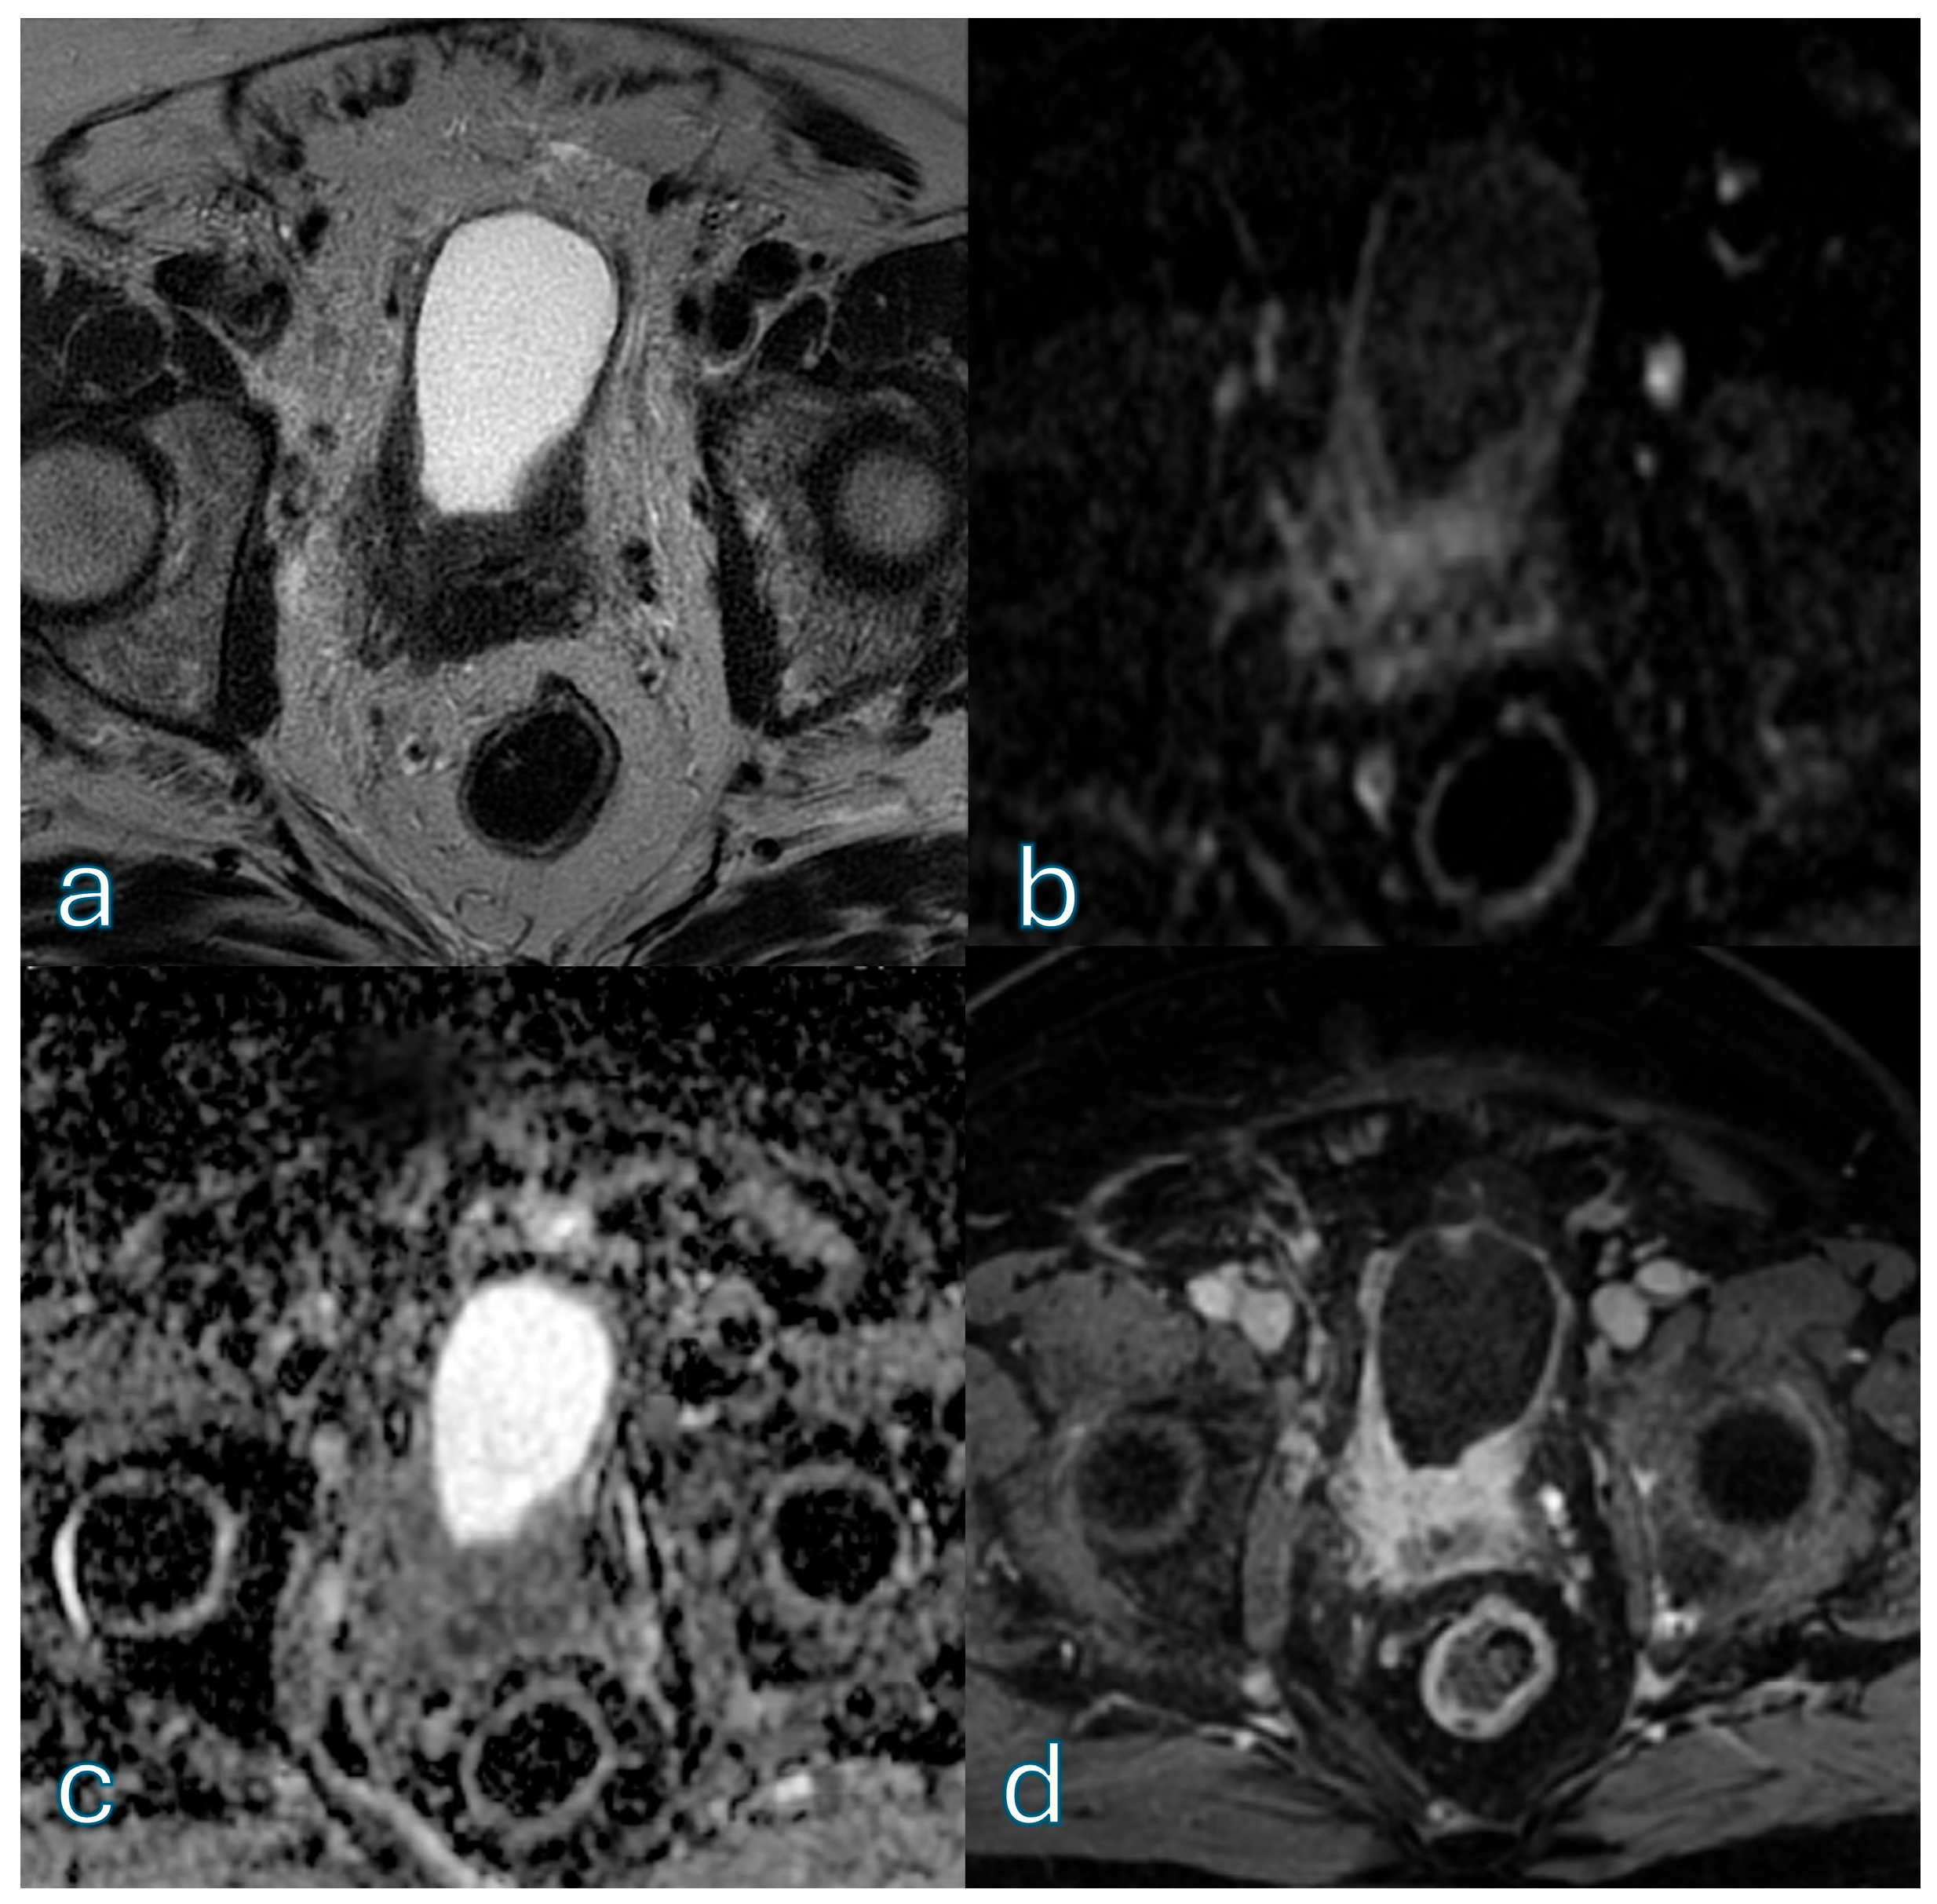

3.4. bpMRI Performance: Non-Expert Reader